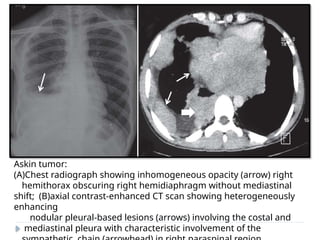

ASKIN TUMOR

⚫ Aggressive malignant tumor of primitive

neuroectodermal origin.

⚫ Mostly arise from the soft tissues of the chest wall or

lung

periphery.

⚫ Children & adolescents.

⚫ IMAGING :

⚫ U/L involvement usually seen

⚫ Nodular pleural thickening

⚫ Infiltration into the chest wall, mediastinum and

sympathetic chain is pathognomic.

⚫ Pleural effusion and rib destruction may or may

not be seen.

Askin tumor:

(A)Chest radiograph showing inhomogeneous opacity (arrow) right

hemithorax obscuring right hemidiaphragm without mediastinal

shift; (B)axial contrast-enhanced CT scan showing heterogeneously

enhancing

nodular pleural-based lesions (arrows) involving the costal and

mediastinal pleura with characteristic involvement of the

ASKIN TUMOR ⚫ Aggressivemalignant tumor of primitive neuroectodermal origin. ⚫ Mostly arise from the soft tissues of the chest wall or lung periphery. ⚫ Children & adolescents. ⚫ IMAGING : ⚫ U/L involvement usually seen ⚫ Nodular pleural thickening ⚫ Infiltration into the chest wall, mediastinum and sympathetic chain is pathognomic. ⚫ Pleural effusion and rib destruction may or may not be seen.

Askin tumor: (A)Chest radiographshowing inhomogeneous opacity (arrow) right hemithorax obscuring right hemidiaphragm without mediastinal shift; (B)axial contrast-enhanced CT scan showing heterogeneously enhancing nodular pleural-based lesions (arrows) involving the costal and mediastinal pleura with characteristic involvement of the